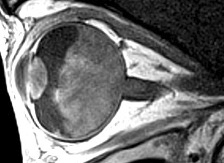

Figure 19 IRM montrant un rétinoblastome sans extension extraoculaire.